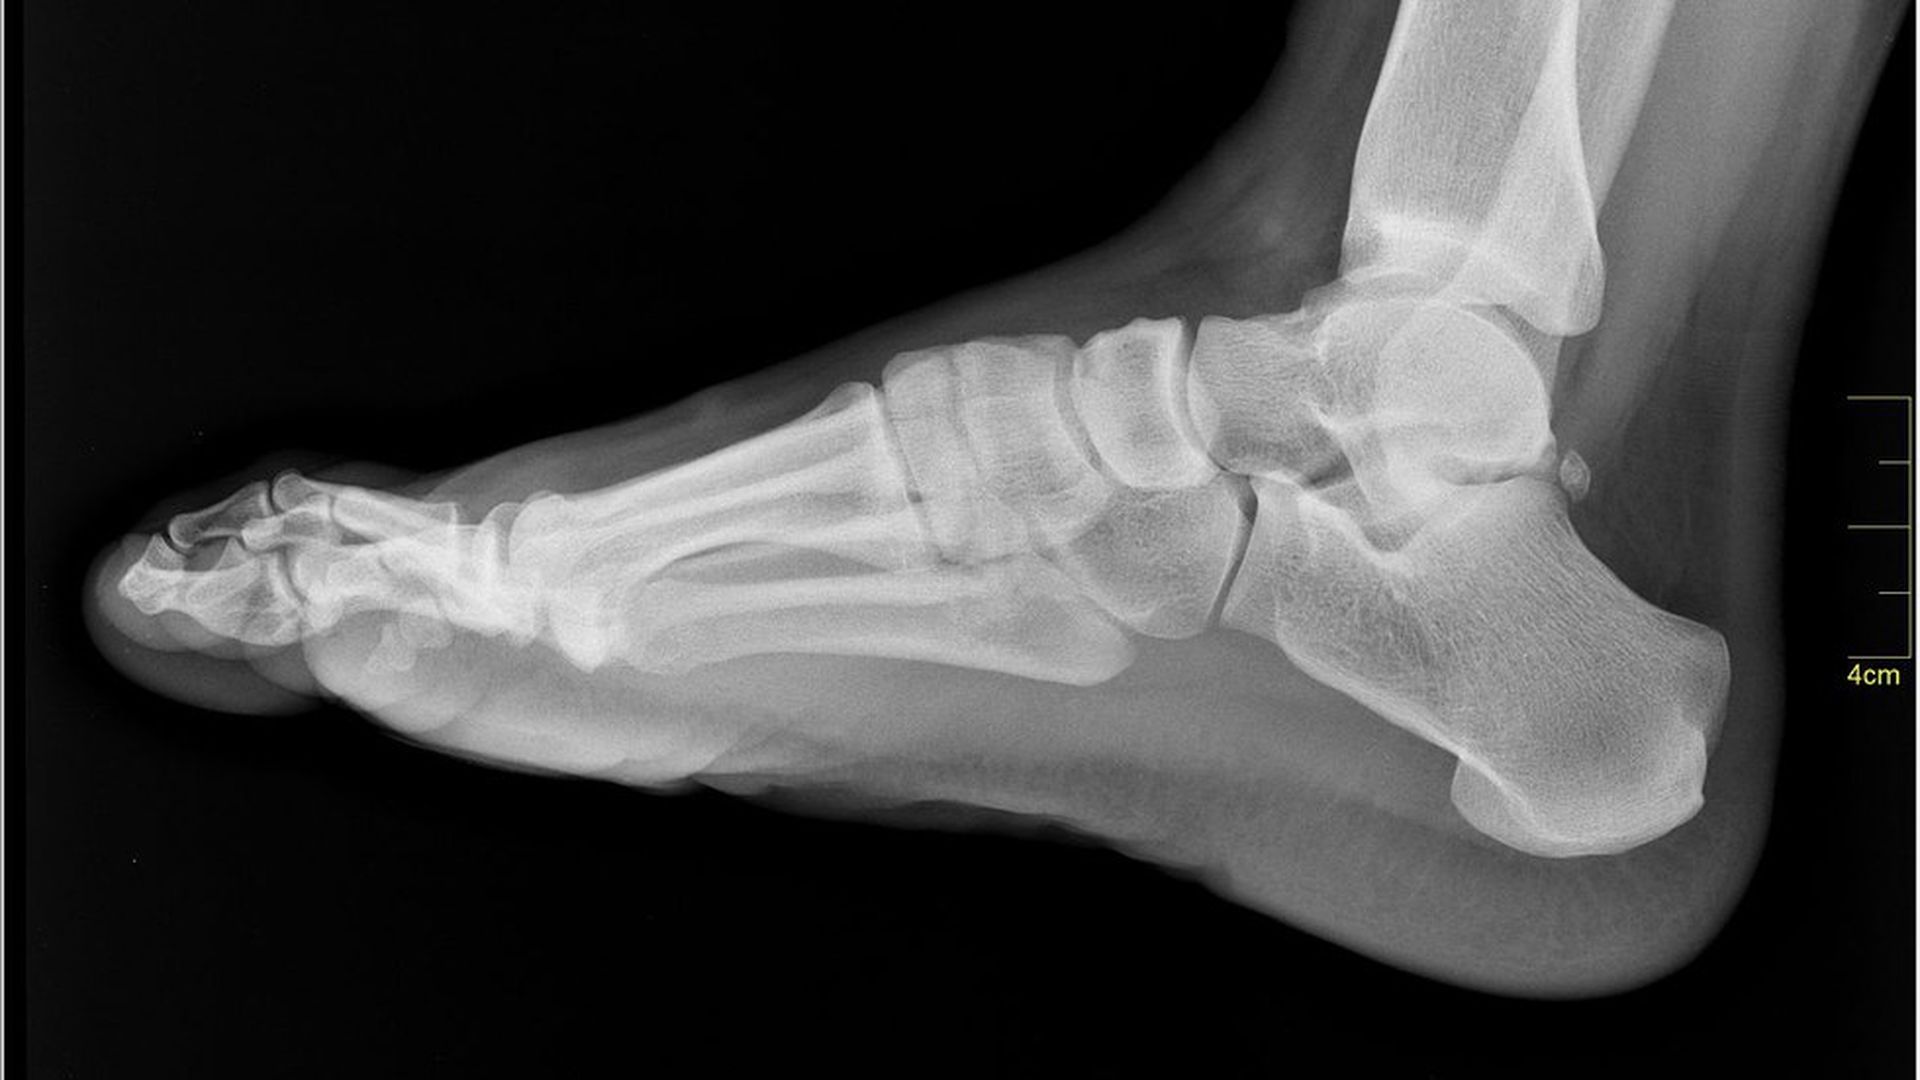

Nevit Dilmen / Wikimedia Commons